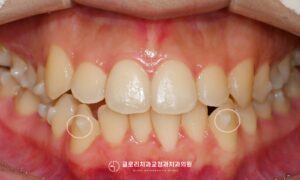

안녕하세요.상봉동 교정치과 김정은 원장입니다. 오늘은 총생과 정중선 편위가 동반된 부정교합을상악골 확장장치를 활용한 비발치 교정으로 치료한 케이스를 소개드리려 합니다. 총생은 치아가 자랄 공간이 부족해 치열이 겹치거나 틀어지는 상태를 말하는데보통 전치부에서 두드러지게…